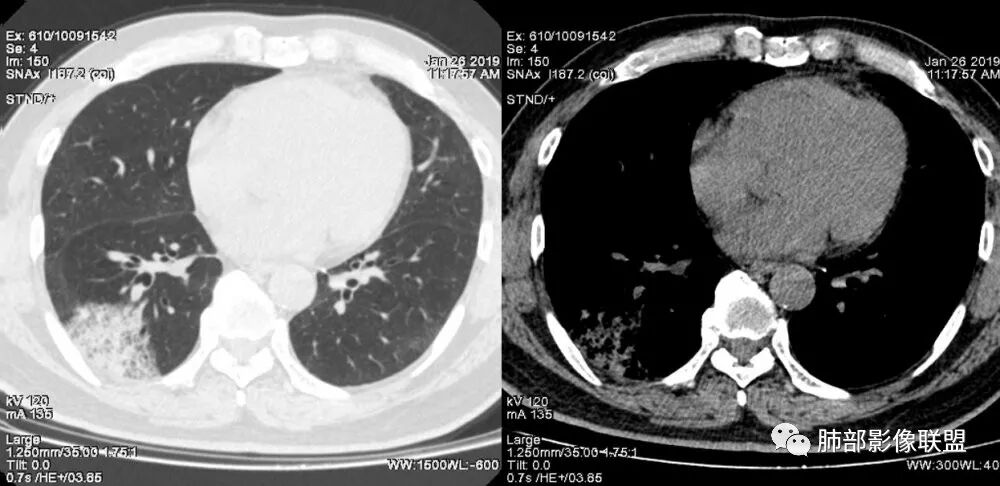

老年女性;右下肺混合实变影,呈楔形改变,边缘清晰,支气管进入且扩张,蜂窝状改变,考虑粘膜相关淋巴瘤,鉴别粘液腺癌,肺栓塞。

女,55咳嗽咳痰,右肺下叶片状实变,磨玻璃影及蜂窝影,考虑粘液腺癌。

右肺下叶大片状影,密度不均匀,部分实变部分磨玻璃,大部分病灶尚清晰,其内支气管稍扩张,中年女性,首先考虑粘液腺癌,待鉴别淋巴瘤,常规抗炎治疗后复查。

中年女性,右肺下叶实变,近似扇形,外朝内发展趋势,外围紧贴胸膜面,中心密度略高,边缘密度略低,病灶内支气管略扩张。考虑肺炎型肺癌。常规建议抗炎治疗后复查,如无变化或变化不明显,建议穿刺活检。

胸膜下,实变,毛玻璃影,囊,边界清,枯枝,粘液腺。

老年女性,右肺下叶大片实变,小叶间隔及小叶内间隔增厚,边界较清,其内支气管似乎可见稍扭曲,分支减少。考虑1.肺炎型肺癌2.结合临床除外类脂性肺炎。

起源于胸膜下,实性成分,边缘Ggo,边界清晰,内可见小叶间隔增厚,粘液腺癌可能。建议先消炎后复查。

右肺下叶胸膜下大片状MGGO,其内结构紊乱,可见空泡征,病灶内近端支气管扩张,远端闭塞,形态不规则,边界部分清楚,部分似清非清,考虑粘液腺癌,鉴别淋巴瘤

该病灶主病灶位于胸膜下(肋膈角处),边缘膨隆改变,周围毛玻璃,边界清楚,病灶内支气管僵直,轻度扩张,小分支无,符合枯树枝改变,有多发小空泡(难与支气管区别),应该符合肺炎性肺癌,但无蜂窝,没有增强无法判断有无粘液、血管特点,如果周围显示的空泡是支气管,其已达到远端,这些有符合炎性特点,工作中,我会先抗炎膨后复查再定。

这是潘老师说的外向内吗?右下实变,蜂窝,GGO,支气管变形迂曲,局部膨胀感,肺炎性肺癌,粘液腺癌可能。常规先抗炎再复查。鉴别淋巴瘤,淋巴瘤支气管一般不变形,壁光整,病程长。

3.病灶内支气管走形略显僵直,侧支少(粘液阻塞),也符合肺腺癌的枯树枝征。而大叶性肺炎的支气管是管壁光整、通畅、自然,结核的支气管常常壁增厚,甚至狭窄后扩张;

4.患者临床症状不重,临床炎性指标不高,结合肺内影像,应警惕肺炎型肺癌。